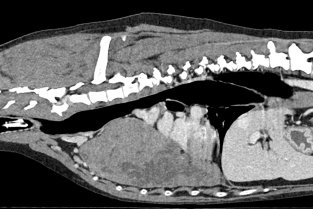

Les journées annuelles du Groupe d'étude en Oncologie (GEO) se consacreront à un focus sur les tumeurs cachées (intrathoraciques, costales, médiastiales, pulmonaires…) et sur des tumeurs de localisation rare (tumeurs rectales, ou périanales, comprenant les carcinomes des sacs anaux) : comment les mettre en évidence, en diagnostiquer la nature, les prendre en charge, de la chirurgie à la thérapie adjuvante ou palliative. Enfin, comment évaluer la qualité de vie des animaux cancéreux et améliorer la prise en charge aussi sur ce plan-là.

- Reconnaître les manifestations cliniques des masses intrathoraciques et les localiser (pleurales, médiastinales, pulmonaires, costales).

- Utiliser l’imagerie (échographie, scanner) et savoir quand recourir à une ponction ou une biopsie intrathoraciques.

- Évaluer le pronostic et les options thérapeutiques des masses pulmonaires, y compris en cas de nodules métastatiques.

- Différencier, lors de masse médiastinale, un lymphome d’un thymome et connaître leur traitement et leur pronostic.

- Diagnostiquer et traiter les tumeurs de la paroi costale, ainsi que les tumeurs cardiaques et de la région périanale chez le chien, avec leurs approches spécifiques (chirurgie, radiothérapie, traitements adjuvants ou interventionnels).